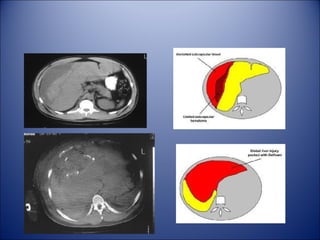

• CT Scan

– The standard evaluation method for stable pt

– Performed with water soluble oral and

intravenous contrast

• CT Scan – The standard evaluation method for stable pt – Performed with water soluble oral and intravenous contrast